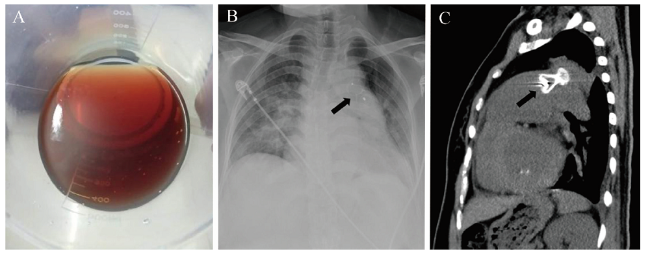

患者女,46岁。因出现黄疸、酱油色样尿2周于2019年5月16日入院。入院前2周患者因PDA(窗型)于外院行经皮PDA封堵术,术后当晚即出现酱油色样尿(图1A),考虑诊断为封堵术后机械性溶血,予对症治疗(具体治疗方案不详)后,酱油色样尿未见明显好转,遂转至我院。患者既往史及家族史等均无特殊。

图1 一例PDA封堵术后重度溶血患者相关检查图

注:A为PDA封堵术后持续存在的血红蛋白尿;B为术前胸部X线正位片,箭头所示为PDA封堵器;C为术前CT检查提示动脉导管内见高密度金属影,最窄处直径8.75 mm,箭头所示为PDA封堵器。

血常规:血红蛋白55 g/L,红细胞1.74×1012/L,白细胞17.91×109/L,中性粒细胞14.99×109/L,血小板计数48×109/L。肝功能:总胆红素31.5 μmol/L,间接胆红素23.8 μmol/L。尿常规:潜血(+++),尿红细胞114.4个/μL,尿蛋白(+)。经胸超声心动图:PDA封堵术后,封堵伞周边可见7 mm残余回声失落,二尖瓣中度关闭不全。胸部X线正位片、CT平扫:主动脉弓与肺动脉干之间见高密度金属影,PDA封堵术后改变(图1B、C)。